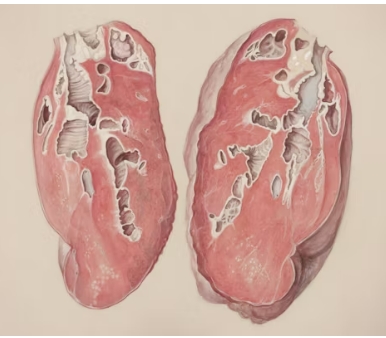

둘째, 염증성 결절입니다. 폐결핵과 같은 감염성 질환이나 자가면역질환 등으로 폐에 염증 반응이 일어나면서 결절이 생길 수 있습니다.

셋째, 염증 후 반흔 결절로, 과거의 염증이 치유되면서 흉터처럼 섬유성 조직이 남아 결절이 되는 경우입니다.